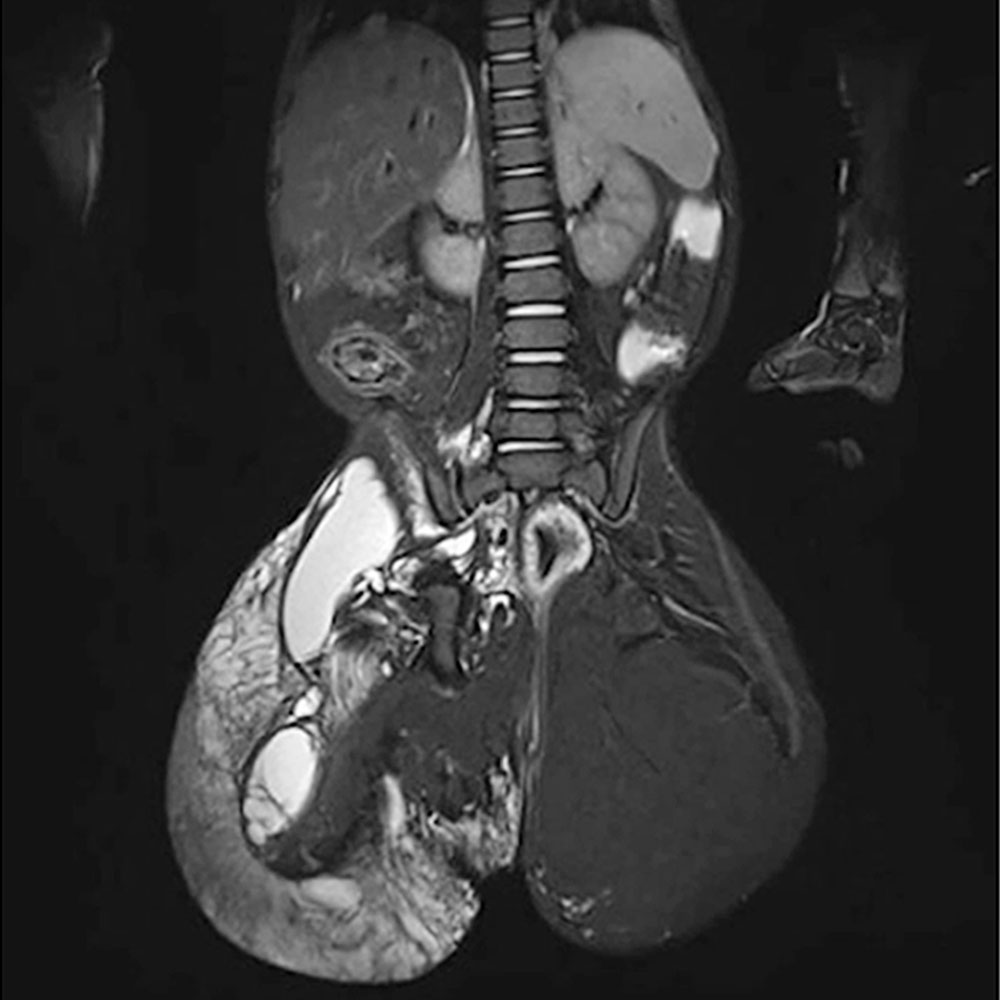

Bei Patienten mit Gefäßanomalien sollte in der Regel nach Diagnostik einer Skoliose ein MRT der Wirbelsäule folgen, um unterscheiden zu können, ob die Wirbelsäulenverkrümmung auf eine Gefäßmalformation im Bereich der Wirbelsäule selbst (z. B. beim CLOVES-Syndrom) oder eine mögliche Beinlängendifferenz zurückzuführen ist. Oder aber, ob es sich um eine idiopathische Skoliose handelt, die unabhängig von der Gefäßmalformation bei dem Patienten vorhanden ist.

Zudem sind die Wirbelkörper selbst oder ihre unmittelbare Umgebung zuweilen in die Gefäßmalformation einbezogen in Sinne einer Durchsetzung mit pathologischen Gefäßen. Dies erschwert die operative Behandlung der Skoliose erheblich und erfordert eine vorherige interventionelle Sanierung dieser Gefäße (z. B. mittels Sklerosierung oder Embolisation).